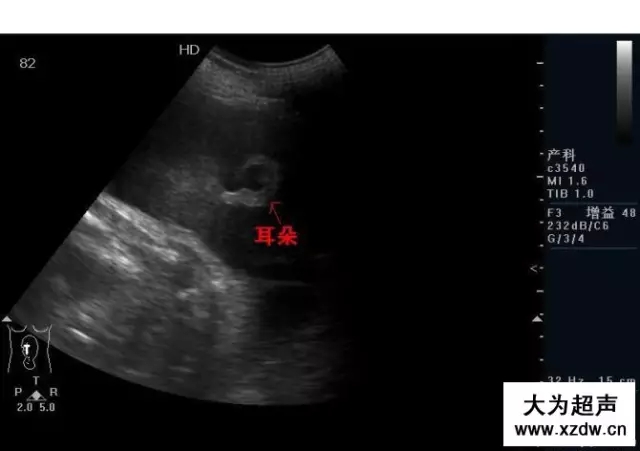

產科超聲正常圖片